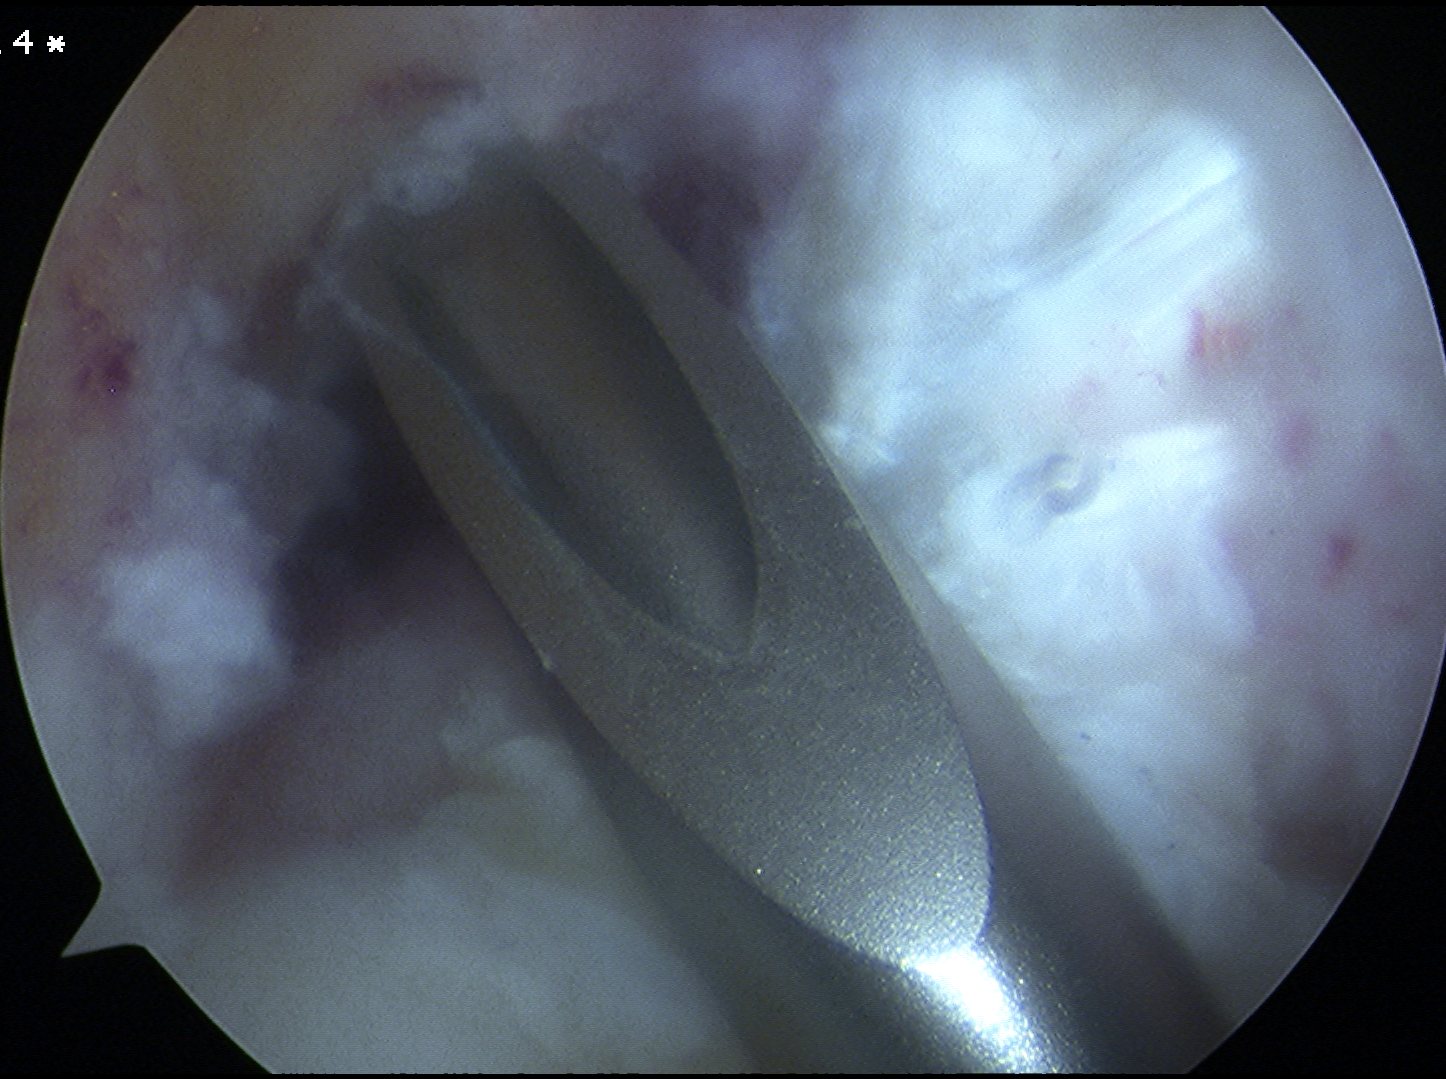

Transtibial femoral tunnel

- need to use 7 mm offset jig to prevent posterior wall blowout

- pass femoral beath pin at 90o

- drill femoral tunnel 10 mm wide

- 5mm deeper than bone graft length

- if bone plug 20 mm long, drill 25 mm

- if bone plug 25 mm long, drill 30 mm

- need to thoroughly clean tunnel of bone debris

- can help to pass acorn reamer twice